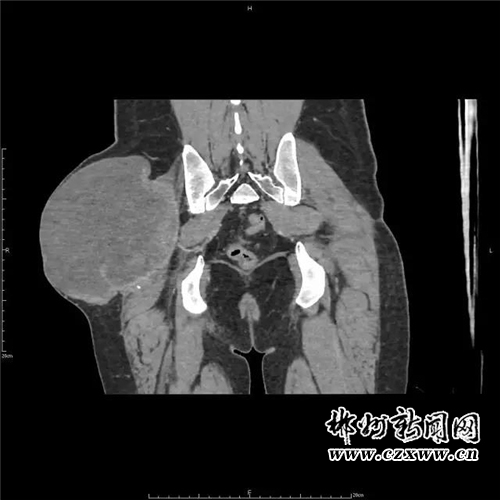

近日,患者感觉肿块突然增大并伴疼痛,觉得不能再耽搁了,遂抱以试试看的心态来我院就诊。入住普外科后,科主任李洪春主任医师亲自接诊并仔细为患者检查,患者右侧臀部外侧见约12*14*10cm大小肿物,不规则型,质软,压痛,活动欠佳,边界清,皮肤无溃烂。穿刺可抽出血性液体。立即予以完善臀部CT。

为进一步明确诊断与治疗,科室立即申请医院副院长放射科主任郑海军主任医师会诊探讨,经讨论认为:患者血管瘤营养支可能来自右侧髂内动脉分支臀上、下动脉,血运丰富,血流量大,一旦再次出血,后果将不堪想象,应尽快安排手术取出该“定时炸弹”。可问题是,该肿块血运如此丰富,术中出血不可估量,该如何避免呢?此时,李洪春主任立即联系介入科主任薛小刚副主任医师会诊,会诊后立即行血管介入栓塞术,以先切断肿块的血运,防止术中大出血。行血管介入栓塞术后,再在做好其他术前准备和积极备血的前提下,普外科予患者行右侧臀部巨大假性动脉瘤切除术。